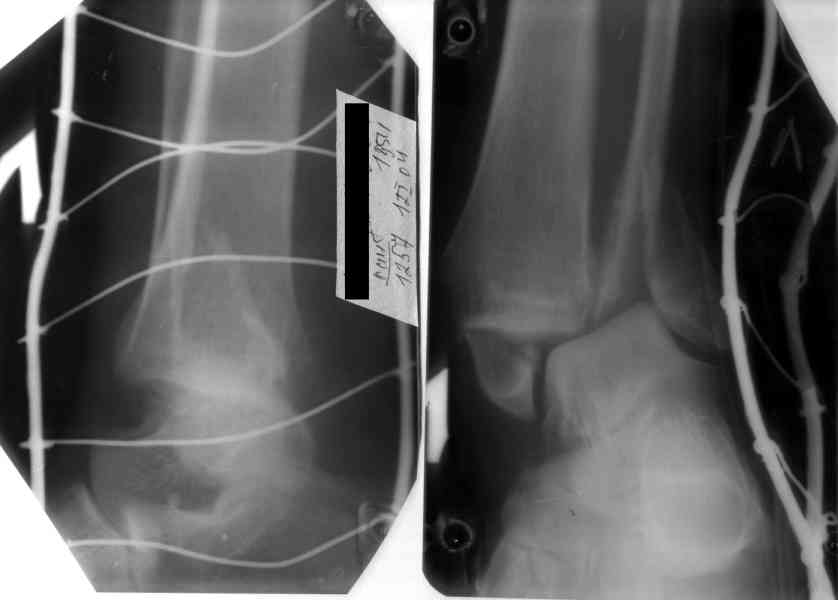

Удалены спицы, а гипса не было? 3-х лодыжечный перелом фиксировать 4 недели недостаточно. Что и подтверждается на последнем снимке - есть тенденция к подвывиху кнаружи, кзади... Что будет дальше, когда пациент начнет давать полную нагрузку?

Малоберцовая выглядит коротковатой. Профиль как-то мутный. Вообще, неплохо было бы сделать снимки в сравнении со здоровой.